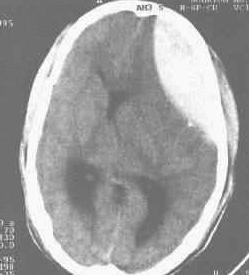

(二)顱腦外傷及腦腫瘤(craniocerebral trauma and cerebroma)

用於急性顱腦外傷及腦手術後的藥品2.顱腦腫瘤:可因腫瘤部位、性質及生長的速度不同而表現不同程度的意識障礙。急性發展的腦腫瘤,隨著腫瘤的迅速增長和顱內壓的增高,表現反應遲鈍、意識模糊、情感淡漠、嗜睡、注意力不集中等,嚴重時出現意識混濁直至昏迷。其中以額葉、胼胝休、垂體和間腦腫瘤引起嗜睡狀態者為多。間腦腫瘤以嗜睡狀態為其特徵,其嗜睡常呈發作性不可抗拒的睡眠狀態,發作時可伴有短暫的肢體無力,可在病人大哭或情緒波動時所誘發。除嗜睡狀態外,常伴有發作性意識障礙或意識喪失,這種意識障礙發作時出現肌肉過度強直,頭向後仰等。聶葉腫瘤時常以鉤回發作為其特點,發作前常有味及嗅幻覺為先兆。爾後意識模糊,常有夢境般的體驗,並有舔舌,吮唇等自動動作。顱腦腫瘤的特點為:①具有顱壓增高的症狀:頭痛、嘔吐、視乳頭水腫。②具有神經系統定位陽性體徵。③有意識障礙和其他精神症狀。④腦脊液、腦電圖和CT檢查可確定腫瘤的部位和性質。